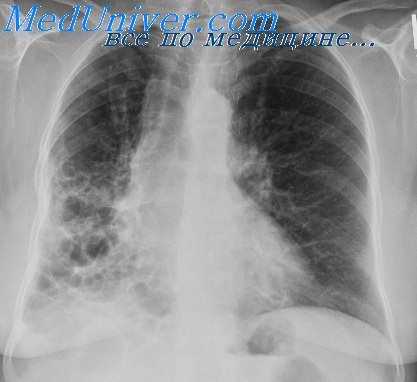

Рентгенологическая картина после торакопластики. На обзорных рентгенограммах и томограммах после экстраплевральной Т. определяется уменьшение объема оперированной половины грудной клетки и спадание соответствующего легкого. Степень уменьшения объема грудной клетки и легкого на оперированной стороне зависит от вида и объема Т. Рентгенологические изменения в легких наблюдаются при возникновении пневмонии, иногда осложняющей послеоперационное течение. В первые дни после операции могут возникать массивные ателектазы, в свою очередь осложняющиеся пневмониями. После обширной Т. может наблюдаться флотирование (маятникообразное смещение, синхронное с дыханием) средостения в области дефекта грудной стенки, исчезающее по мере регенерации костной ткани из оставшейся надкостницы ребер.

В отдаленные сроки после операции спавшееся легкое частично расправляется и вентиляция его улучшается за счет увеличения амплитуды дыхательных движений диафрагмы и ребер на стороне оперативного вмешательства, что отчетливо определяется на рентгенокимограмме (см. Рентгенокимография). В ряде случаев расправления легкого в отдаленные сроки не происходит вследствие развития в нем после операции пневмосклероза (см.), а иногда в последующем — бронхоэктазов (см.).

Определяемые после Т. тени регенерировавших ребер, особенно на фоне массивных плевральных шварт, затрудняют распознавание остаточных каверн и щелевидных остаточных полостей эмпием в случае неэффективной операции. Томография (см.) облегчает диагностику каверн в спавшемся легком, а фистулография (см.) и бронхография (см.) — выявление остаточных полостей.

У всех наблюдаемых нами больных был фиброзно-кавернозный туберкулез легких в фазе распада, инфильтрации и обсеменения. Размеры каверн колебались от 3 до 18 см. При наличии у большинства больных больших и гигантских каверн, как правило, отмечалось двухстороннее интенсивное очаговое обсеменение легких. Поэтому, имелась выраженная редукция функции внешнего дыхания, причем, преобладал ресгриктив-ный (ограничительный) компонент, о чем свидетельствовали снижение должных величин ЖЕЛ, МВЛ и коэффициента резерва у значительной части больных.